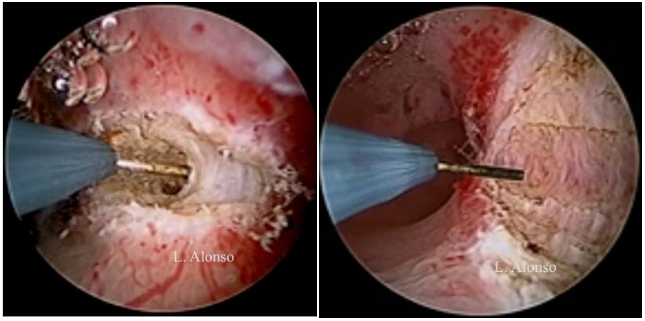

宫腔镜子宫成形术是在子宫纵隔上划开一个横行切口取代了切除。这个切口应在纵隔中间划开,与宫腔前后壁距离相等。参照输卵管开口进行手术有助于保持切口水平,避免损伤正常子宫肌层。选择正确的切口位置是宫腔镜子宫成形术最重要的一部分,但是选择合适切口并不容易。Levent Yasar 和 Ali Süha  发现在亚甲蓝注射后,有2-3mm的蓝色的线,在输卵管开口之间跨过纵隔并且与宫腔前后壁等距离,称此为“Süha-Levent 线” 。这条蓝色的线可以帮助他们选择正确的切口位置。

发现在亚甲蓝注射后,有2-3mm的蓝色的线,在输卵管开口之间跨过纵隔并且与宫腔前后壁等距离,称此为“Süha-Levent 线” 。这条蓝色的线可以帮助他们选择正确的切口位置。

纵隔手术有两种不同的手术方式,薄化技术和缩短技术。薄化技术是在子宫的每一面将纵隔从底部到顶端做纵行切口,目的是减少纵隔的宽度并改善初始宫腔两侧宫角凹陷中间的基底部残余组织。在缩短技术中,纵隔被横向由顶到底的切开,切口位于纵隔中间,向宫腔前后壁切除残余组织。